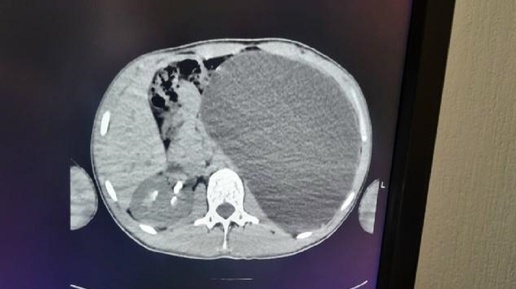

Врачи спасли 17-летнего жителя Новосибирска с гидронефрозом почки. Увеличившийся до гигантских размеров орган мог разорваться в любую минуту. "У нашего пациента почка достигла размеров пятилитровой бутылки! Она занимала почти весь объем живота и давила на все соседние органы. Это была настоящая "бомба замедленного действия": любая травма, случайный удар в живот - и мешок мог разорваться внутри", - рассказали в Детской городской клинической больнице № 1. Опасную патологию выявили случайно. 17-летний парень никогда не жаловался на проблемы с почками и чувствовал себя совершенно здоровым...